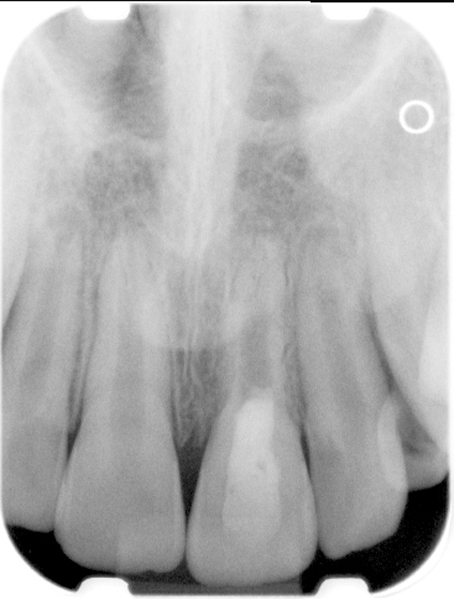

Fig 4. Preoperative radiograph showing aggressive external root resorption and thin dentinal walls.

Figure 4

Fig 5. Working length confirmation.

Figure 5

Fig 6. Postoperative radiograph.

Figure 6

Fig 7. 1-year follow-up showing a healthy lamina dura and root development.

Figure 7

Fig 8. 3-year follow-up showing continued root development.

Figure 8